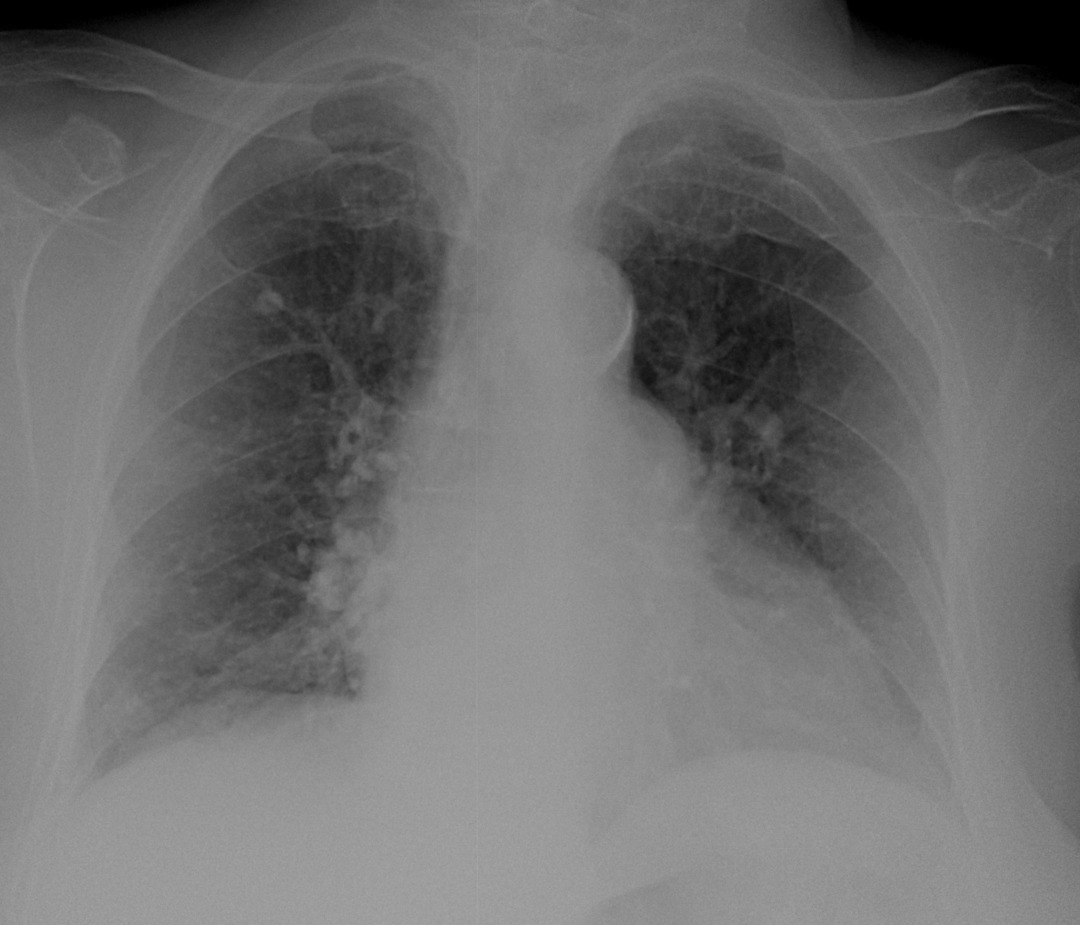

Ж., за 60 лет. На уровне переднего отрезка 2 ребра справа - кальцинат такой крупный?? смущает просветление в центре..

Обычный кальцинат.

Кальцинат, можно архив посмотреть если есть. Еще легочный рисунок усилен за счет сосудистого компонента и митральная конфигурация сердца

Плюсую к митральной конфигурации сердца. Думаю, что в легких не кальцинат, а суммация сосудов. На боковом такое предположение лучше подтверждается, и в "окрестностях" ещё есть сосуды.

Всё-таки кальцинат. Он на тень позвоночника проецируется. И в корнях кальцинаты таже есть.

В любом случае биопсия не требуется, а вот сердце лечить нужно.

Зправа в S2 кальцинат.